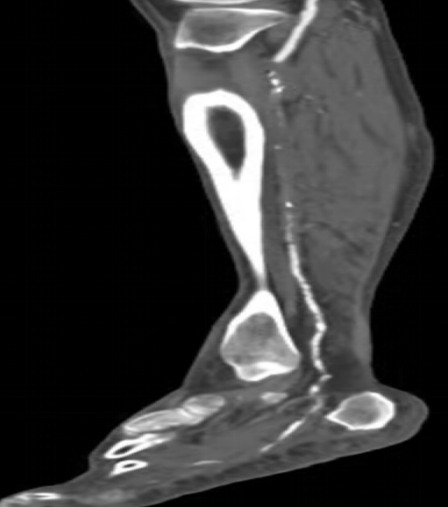

下肢動(dòng)脈CTA

情急之下去了當(dāng)?shù)蒯t(yī)院,醫(yī)生一瞧告訴王大伯:“您這可能是糖尿病足,你這傷口肯定是長(zhǎng)不好了,需要外科手術(shù)清創(chuàng)、植皮,如果還是長(zhǎng)不好就要截肢”。聽(tīng)了醫(yī)生的話,王大伯出了一身冷汗,幾經(jīng)周折最終來(lái)到了我院血液內(nèi)分泌科,住院后進(jìn)行下肢動(dòng)脈超聲及CTA發(fā)現(xiàn):雙下肢膝下動(dòng)脈節(jié)段性狹窄、閉塞。診斷為:右下肢動(dòng)脈硬化閉塞癥(Runtherford6級(jí)),糖尿病下肢嚴(yán)重缺血(右側(cè)),右足潰瘍;經(jīng)多學(xué)科會(huì)診初期"改善循環(huán)、控制血糖、抗感染、局部清創(chuàng)換藥、營(yíng)養(yǎng)神經(jīng)、支持治療"六環(huán)法措施下,老伯潰瘍雖有好轉(zhuǎn),但仍不能完全愈合,右足仍靜息下疼痛。